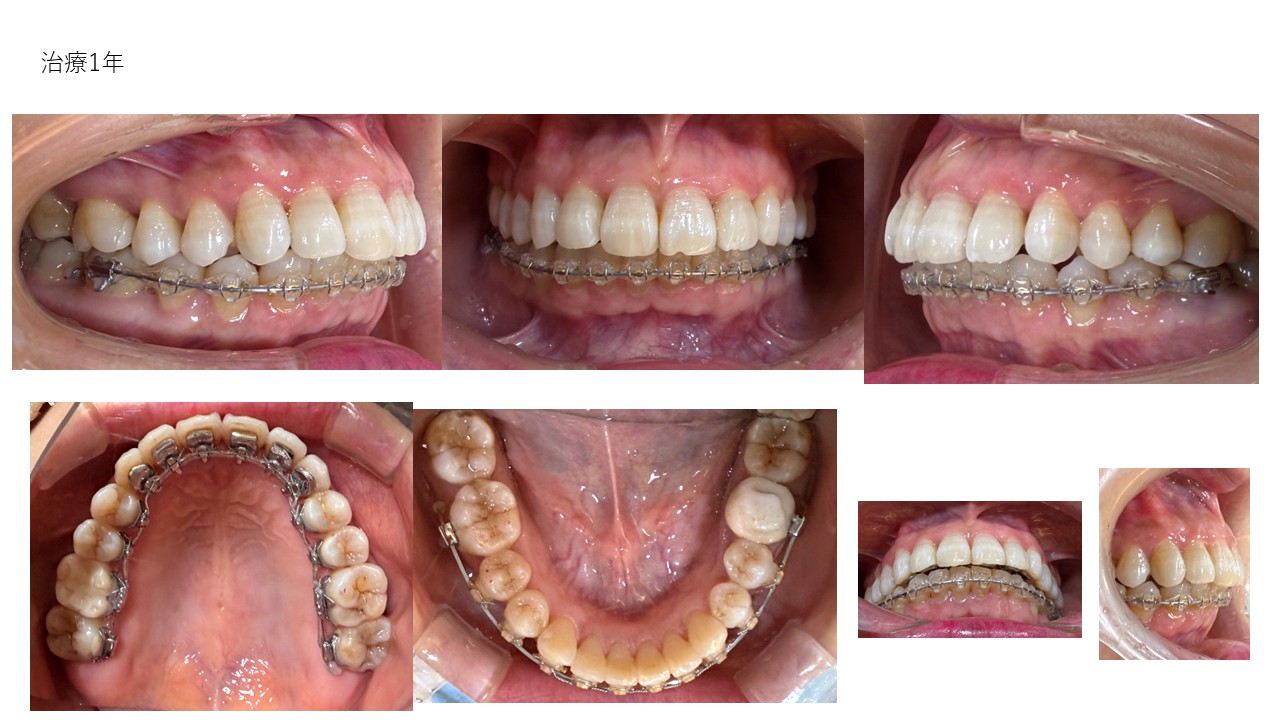

表側ワイヤー矯正

| 主訴 | 叢生、前突 |

|---|---|

| 年齢 | 20代 |

| 治療期間 | 2年4ヶ月 |

| 治療回数 | 19回 |

| 治療に用いた主な装置 | カスタムメイド型マルチブラケットタイプのデジタル矯正装置(インシグニア) |

| 治療費 | 800,000円(税別) |

| 抜歯部位 | 上下顎第一小臼歯4本 |

| リスク・副作用 |

1. 矯正装置を装着すると、不快感や痛みが生じることがあります。通常、数日〜1週間ほどで痛みが消失し、慣れることが多いです。 2. 歯の動き方には個人差があり、予想された治療期間より長引く可能性があります。 |